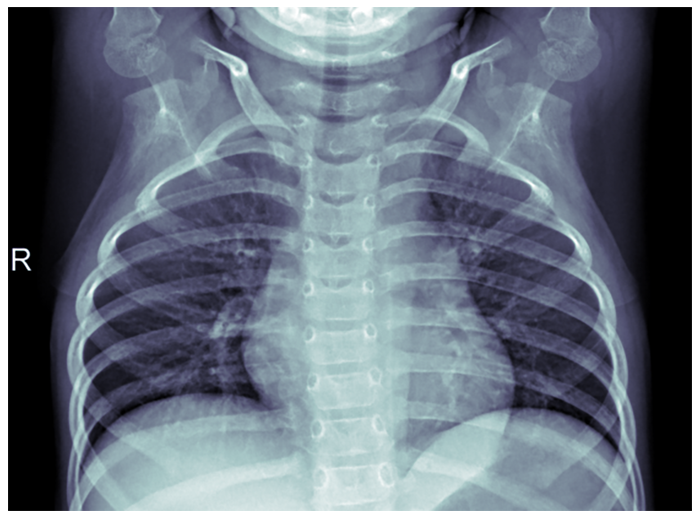

Fig. 5. Radiografie pulmonară - Pneumonie - PAUL MOONEY, 2018 (Chest X-Ray Images (Pneumonia) | Kaggle )

Acesta este locul unde Machine Learning poate fi de ajutor, prin automatizarea procedurii de diagnosticare, care necesită mult timp. În acest exemplu, am folosit librăria TensorFlow împreună cu un model pe TensorHub și setul de date de radiografii toracice de la Kaggle (Fig. 4 este a unui pacient sănătos, iar Fig. 5 este a unui pacient cu pneumonie). Pentru ochiul neexperimentat și chiar pentru cel al unui medic experimentat, acestea ar părea poate greu de distins, ceea ce este de înțeles. Să ne amintim că un medic dedică cea mai mare parte a timpului diagnosticării pacientului și dacă încercăm să distingem cele două scanări putem înțelege de ce.